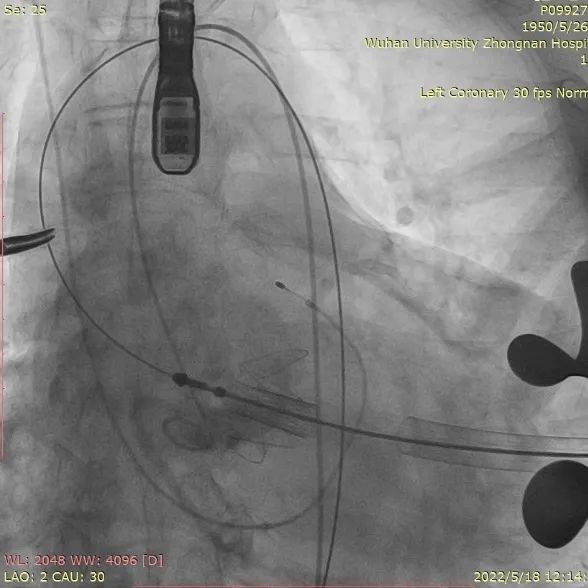

4. 患者术中造影角度LAO:2°,CAU:30°;

术中造影角度:LAO:2°,CAU:30°

1. 患者前降支中段重度狭窄,先行左冠PCI术后,进行TAVR手术;

取平卧位,行右侧股动脉穿刺,置入6F鞘管,注入7000U肝素,分别送EBU3.75、EBU4.0、JL4指引导管均未能到达左冠口,EBU4.0塑型后成功达到左冠口,送VT导丝至前降支远端,送BMW导丝至回旋支远端,送2.0*20mm双导丝球囊于前降支近段狭窄处充分预扩张;送波科3.0*24mmDES一枚至前降支中段病变处,精准定位后释放,分别送3.5*16mm乳突球囊、3.0*15mmNC球囊至支架内修饰扩张。复查造影示支架膨胀良好,撤除鞘管,常规加压包扎,注意有无出血及高迷走反射。

冠造提示左冠前降支狭窄处

PCI后血流通畅